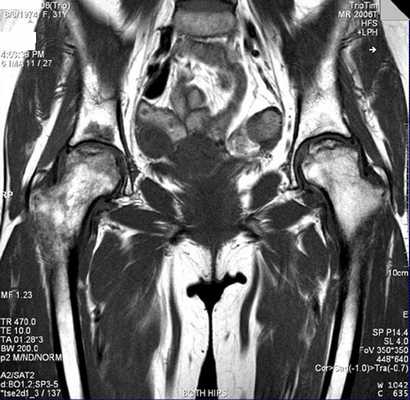

МРТ-артрограмма при послеоперационных изменениях тазобедренного сустава